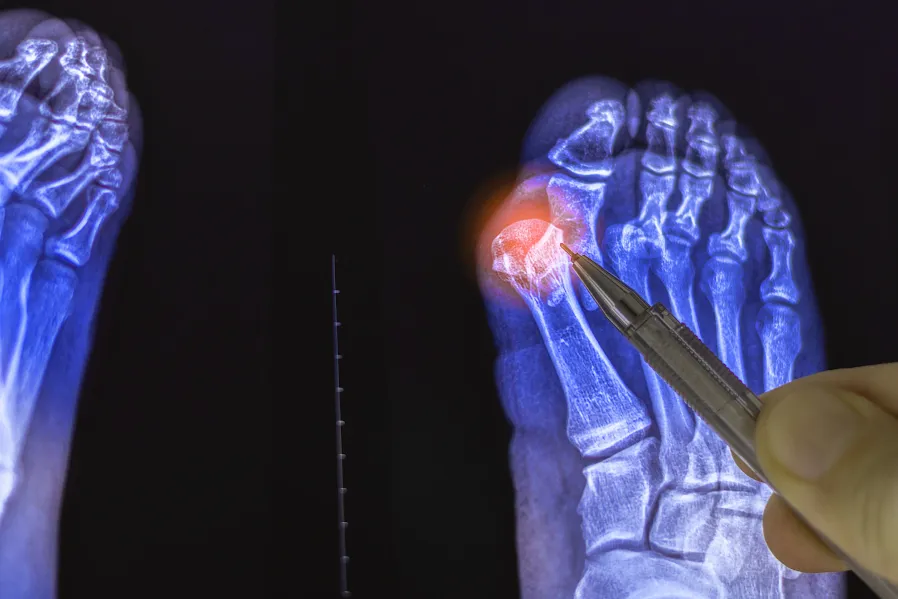

Webinar: Mínima invasión, máxima movilidad: la nueva forma de operar juanetes

Tema: Mínima invasión, máxima movilidad: la nueva forma de operar juanetes